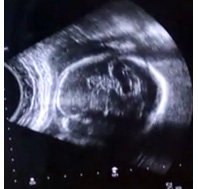

Теперь интересно его личико при рождении такое же будет или еще поменяется,нам 28-ая неделя на фото

на фото кстати незнаю эта закарючка пузырик в околоплодной жидкости или может правда мозг тоже просвечивает